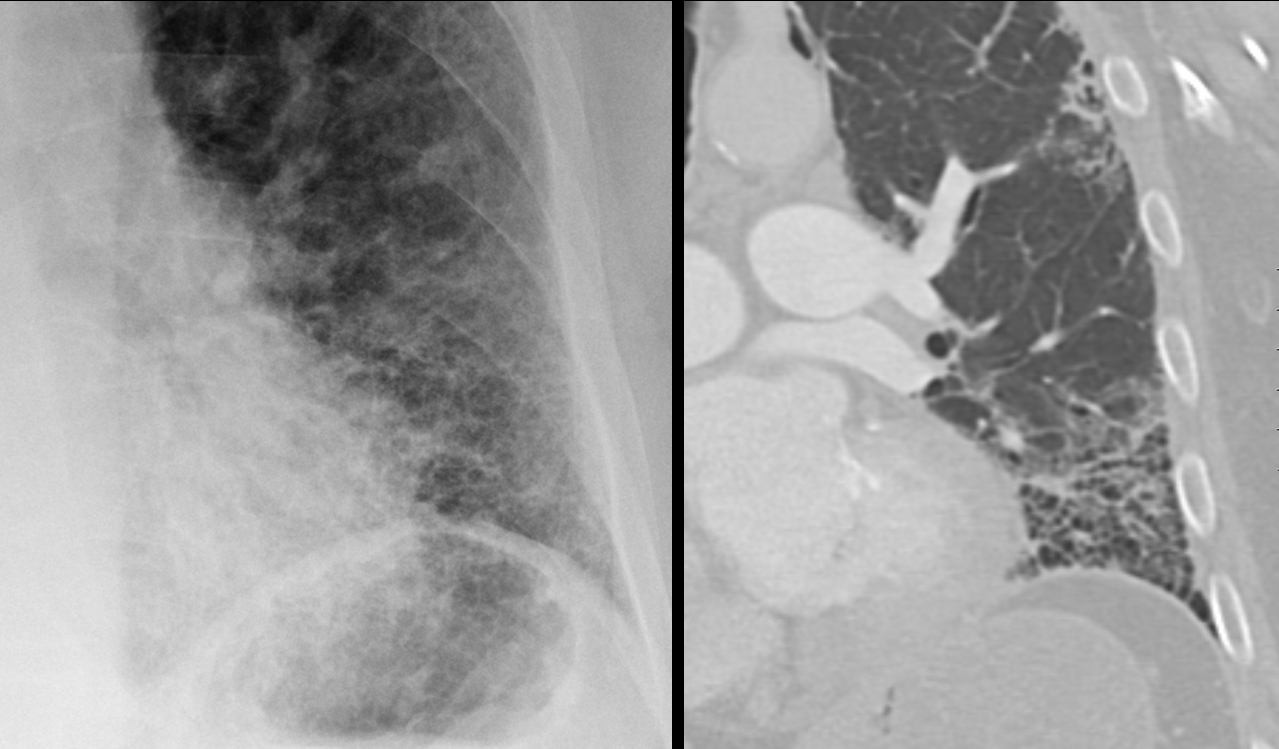

Gallery Pulmonary Fibrosis IPF IPF

IPF